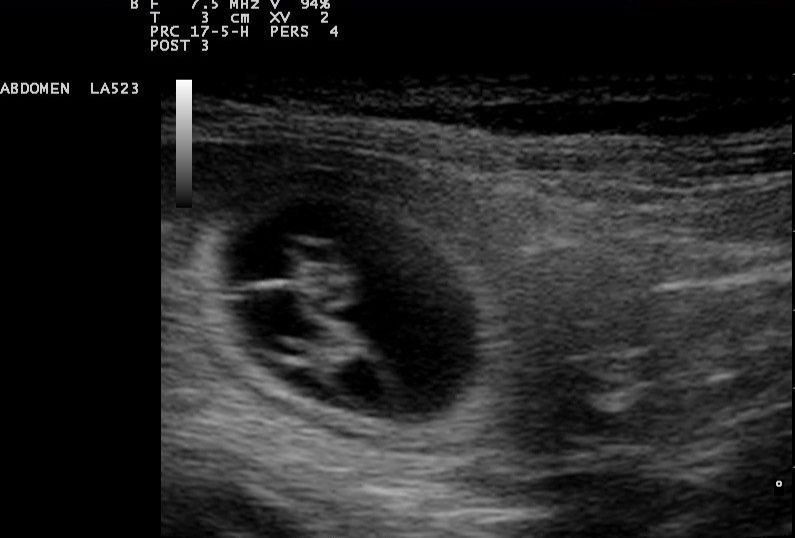

Ultraschall

Die Ultraschalluntersuchung (= Sonographie) ermöglicht die Darstellung von Körperhöhlen und Organen und stellt eine wertvolle Ergänzung zu weiteren diagnostischen Verfahren dar. Neben der bildlichen Untersuchung sämtlicher Organe in Brust- und Bauchraum können ggf. unter Ultraschallkontrolle Gewebe-, Zell- und Flüssigkeitsproben entnommen werden.

Im Brustraum schränkt die in der Lunge vorhandene Luft die Möglichkeiten des Ultraschalls ein. Dennoch ist die Sonographie des Herzens von besonderer Bedeutung.

Sie ermöglicht eine detaillierte Darstellung der Herzinnenstrukturen, aber auch von Ergüssen im Herzbeutel und Tumoren.

In unserem Hause führt unsere kompetente Ultraschallexpertin Fr. Dr. Götzke nach terminlicher Absprache die sonographischen Untersuchungen, sowie EKG und Blutdruckmessungen durch.